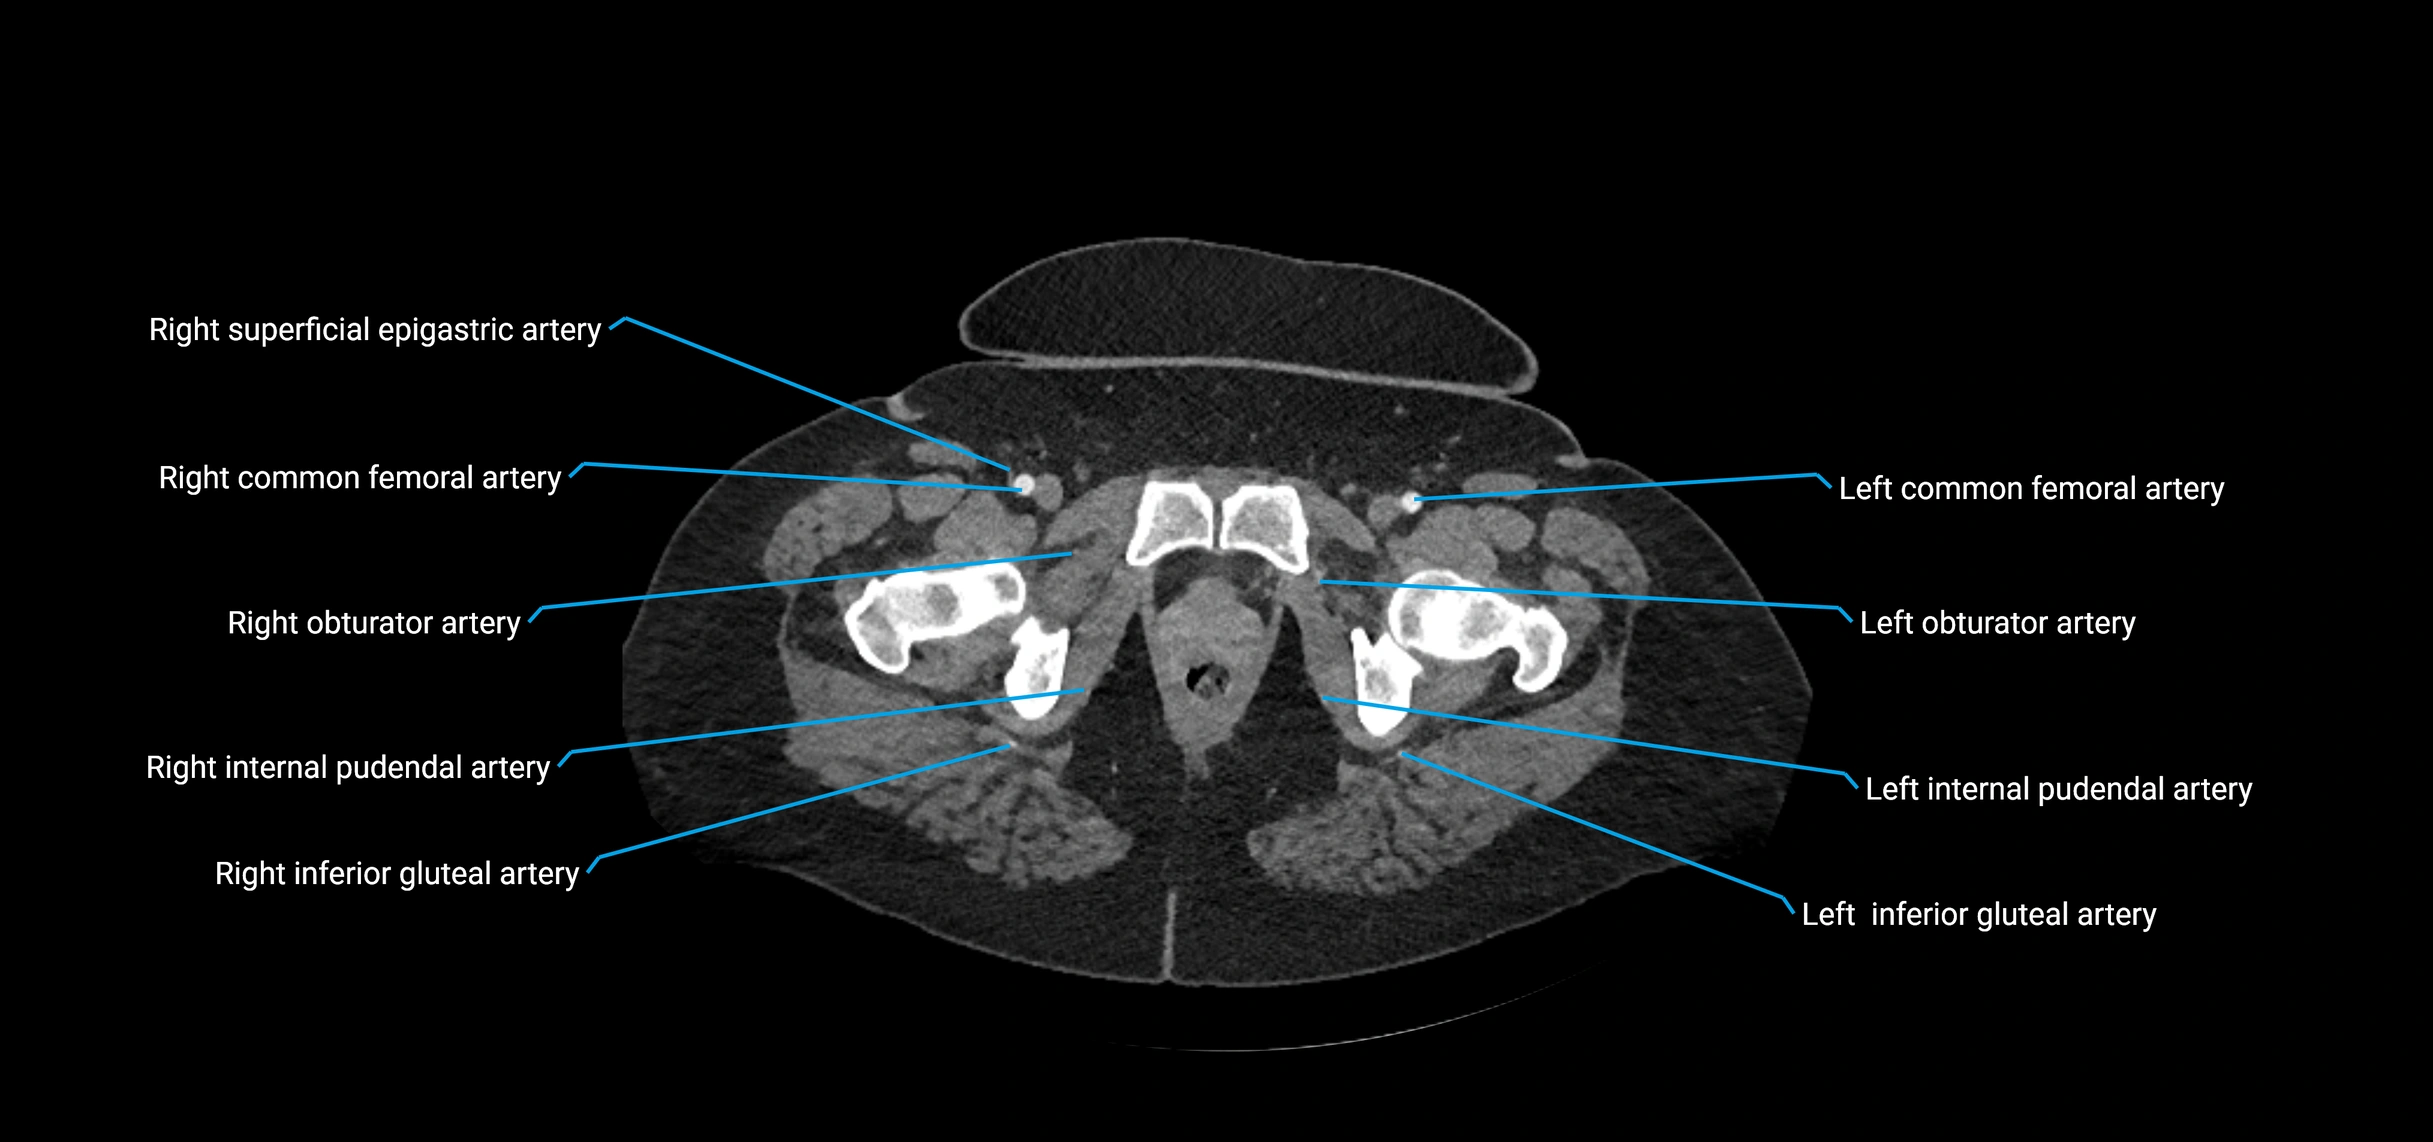

CT images

image

Contrast-enhanced CT (CTA):

• Gold standard for abdominal aortic imaging

• Provides excellent detail of lumen, wall, aneurysm, thrombus, and branch vessels

• Multiplanar and 3D reconstructions help in aneurysm measurement, stent graft planning, and dissection evaluation